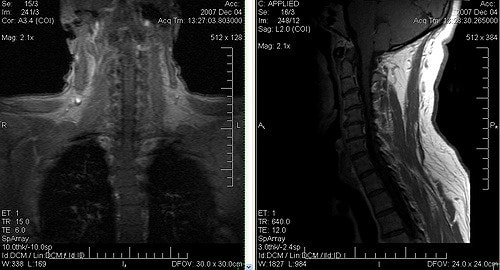

Иногда болит шея и затылок, и причина остается неясной. В таких случаях комплексное исследование сосудов и магнитно-резонансная томография помогут установить точный диагноз и подтвердить мигрень. Это заболевание может затрагивать не только голову, но и шею.

- МРТ шеи и головы.